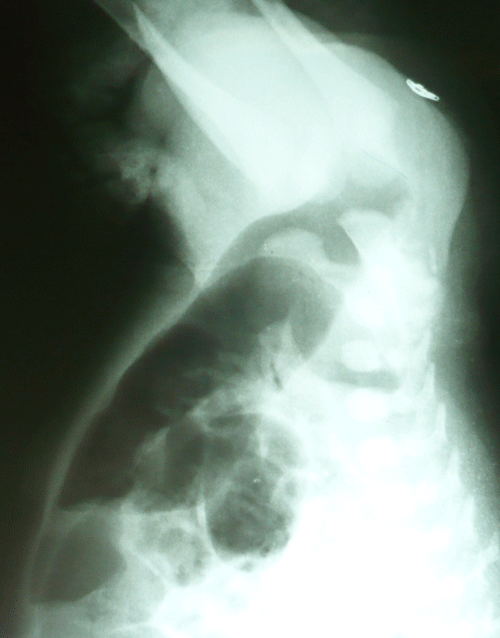

A 36-hour-old male neonate presented with imperforate anus and abdominal distension. There was no meconuria. Antenatal fetal anomaly scanning had not been done. Except for mild tachypnea (respiratory rate 60/min) physical examination of chest was nothing abnormal. Ultrasound of the abdomen did not reveal any anomaly. Invertogram (Fig. 1) showed a high variety imperforate anus. A sigmoid colostomy was performed. The colostomy started moving and patient was allowed orally the following day. The patient developed respiratory distress after starting feeds. A chest radiograph showed eventration of left hemidiaphragm (Fig. 2). A nasogastric tube inserted for gastric decompression alleviated the respiratory distress. The patient underwent plication of the diaphragm electively on 8th day of life. Postoperative recovery was uneventful. The patient is lost to follow-up.

Figure 2: Elevated left hemidiaphragm in the same patient. |